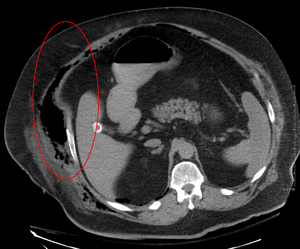

التصوير المقطعي المحوسب (الأشعة المقطعية) على وشك الكشف عن حوالي 80٪ من الحالات بينما قد يتمكن التصوير بالرنين المغناطيسي من الالتقاط أكثر قليلا..[2]

التصوير الطبي

يلعب التصوير دورًا محدودًا في تشخيص التهاب اللفافة الناخر. يعد التأخير الزمني في إجراء التصوير مصدر قلق كبير. قد يُظهر التصوير الشعاعي البسيط انتفاخ الرئة تحت الجلد (غاز في النسيج تحت الجلد)، وهو ما يوحي بشدة بحدوث تغيرات نخرية، ولكنه ليس حساسًا بدرجة كافية لاكتشاف جميع الحالات، لأن التهابات الجلد الناخر التي تسببها بكتيريا المطثية غير المعدية عادة لا تظهر انتفاخ تحت الجلد. إذا كان التشخيص لا يزال موضع شك، فإن التصوير المقطعي المحوسب (CT) والتصوير بالرنين المغناطيسي (MRI) هما الأكثر حساسية من التصوير الشعاعي العادي. ومع ذلك، فإن كلا من الأشعة المقطعية والتصوير بالرنين المغناطيسي ليست حساسة بما يكفي لاستبعاد التغييرات الناخر تماماً.[2] قد يُظهر الفحص بالأشعة المقطعية سماكة اللفافة، وذمة، وغازات تحت الجلد، وتكون خراج.[2] في التصوير بالرنين المغناطيسي، عندما يحدث تجمع السوائل مع وجود التهاب ناخر، أو زيادة السماكة أو التحسين باستخدام حقن التباين، يجب الاشتباه بشدة إلى وجود التهاب اللفافة الناخر. وفي الوقت نفسه، يمكن أن يُظهر التصوير بتخطيط الصدى تكوين خراج سطحي، ولكنه ليس حساسًا بدرجة كافية لتشخيص التهاب اللفافة الناخر.[2] يمكن لفحص التصوير المقطعي المحوسب اكتشاف حوالي 80٪ من الحالات، بينما قد يلتقط التصوير بالرنين المغناطيسي أكثر قليلاً.[12]